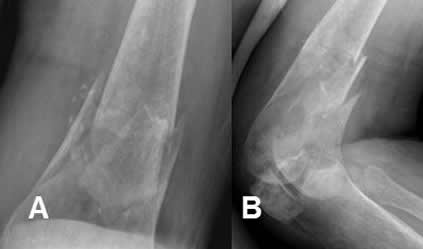

Fig 47. Fractura diastasada.

A: y B: Rx lateral. Fracturas conminutas, rotadas y diastasadas en las diáfisis femorales.